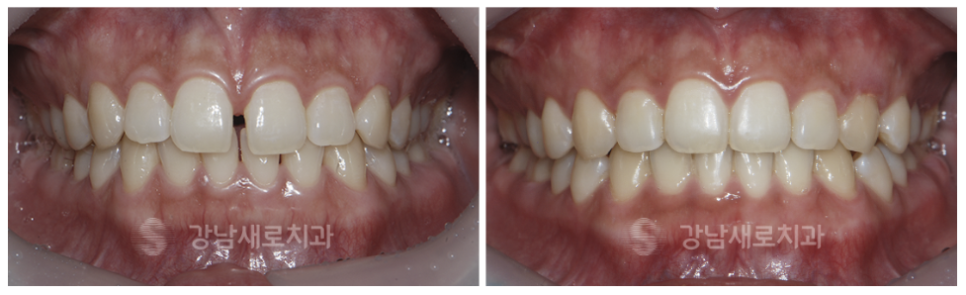

치열이 고르지 못하고 삐뚤빼뚤한

전치부와 송곳니까지

교정을 원하는 치아를 선택하여

치아 라인뿐 아니라 악궁 라인까지

빠르게 개선이 가능합니다.

2018.7 > 2018.11

전방으로 돌출된 치아 한 개도

인접 치아의 라인에 맞춰 후방 이동으로

아름다운 미소를 가능케 합니다.